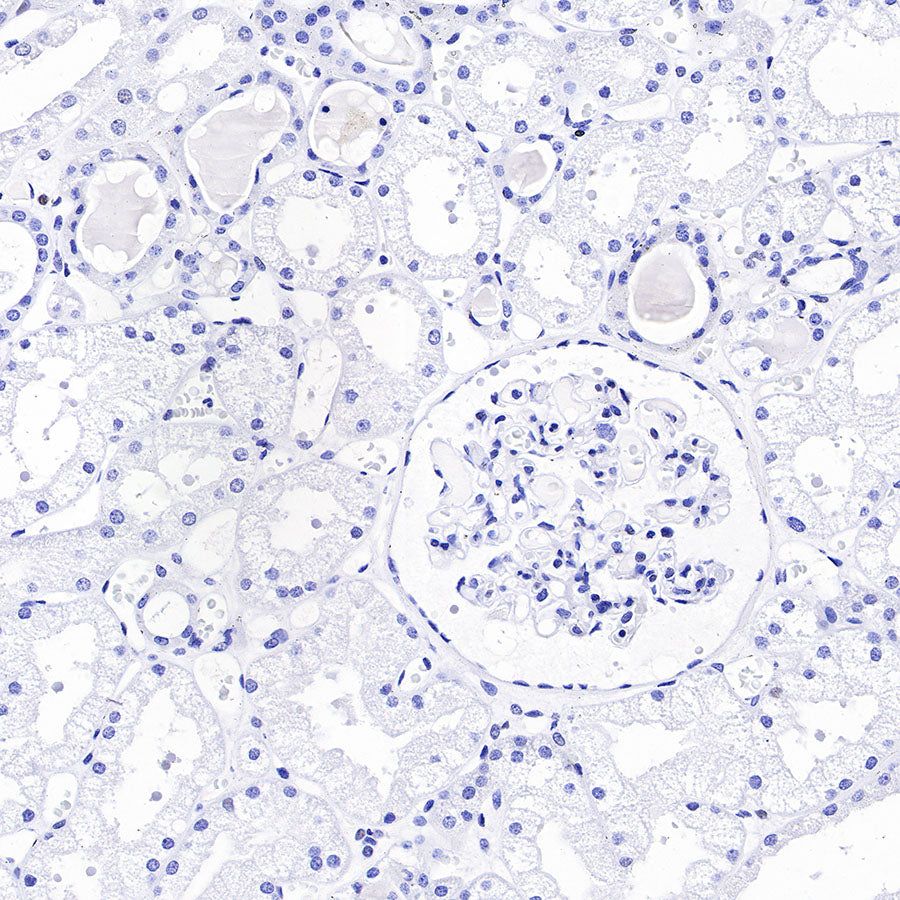

Immunohistochemistry